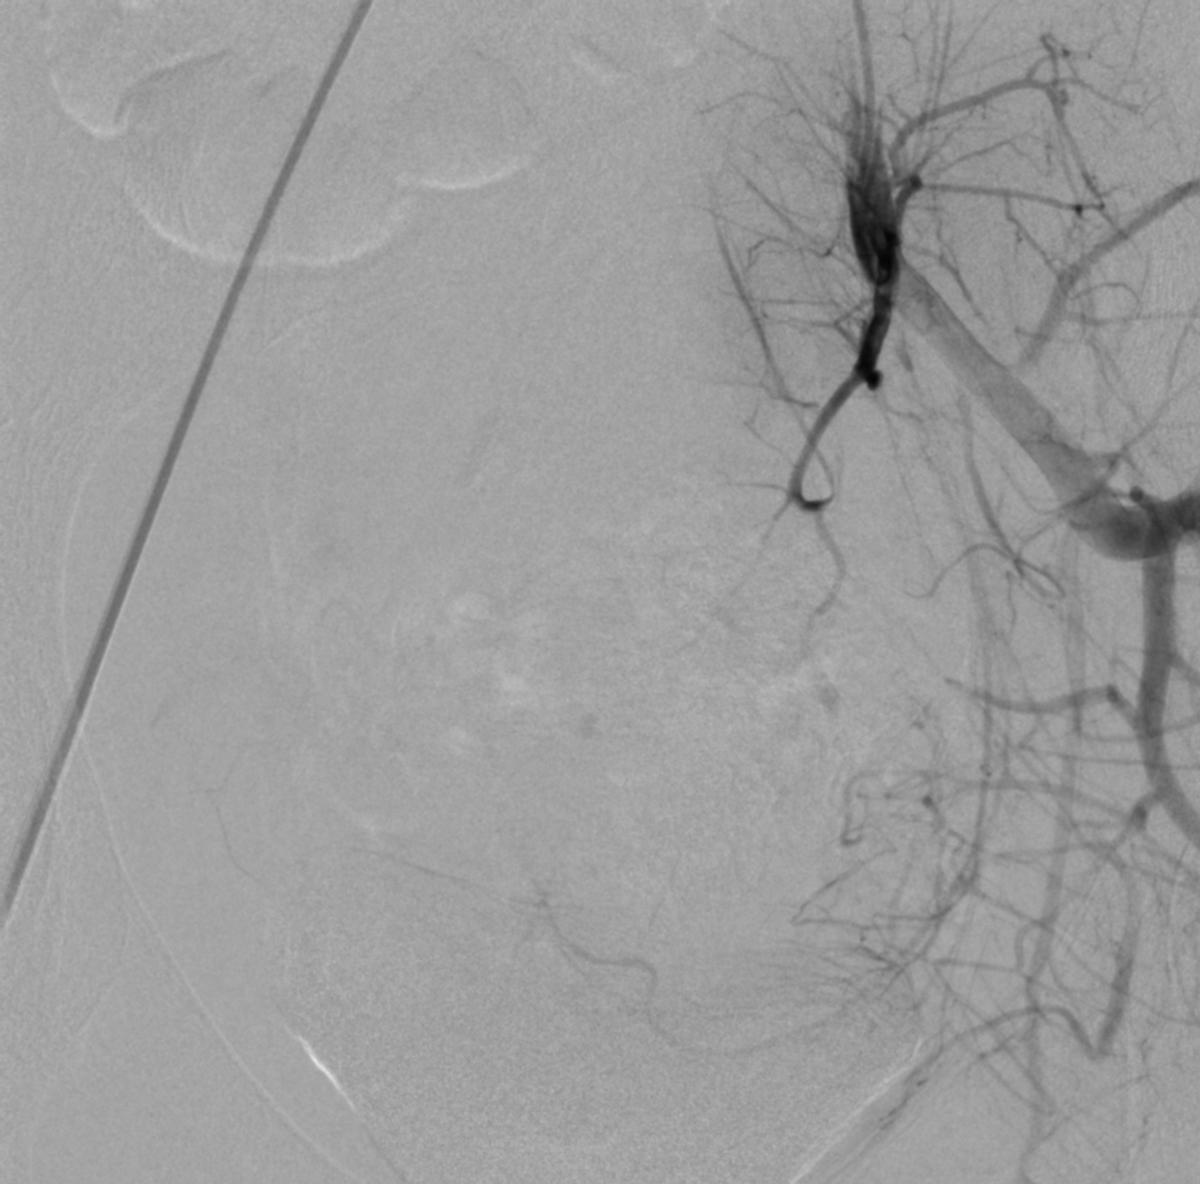

患儿完成入院前术前检查,并进行了全科的术前讨论。结合患儿体征及相关的术前检查,目*考前**虑PROS综合症。目前主要解决的是月经出血的问题,可以通过栓塞双侧子宫动脉来进行治疗。患儿全麻后,使用5F穿刺针行右股动脉穿刺,成功后置入5F血管鞘,导丝引导下置入5F Headhunter Angiopointer造影导管,在导丝引导下选入髂内动脉,进入子宫动脉,造影见左侧子宫动脉远端纤细,右侧子宫动脉螺旋增粗,微导丝引入微导管进入子宫动脉,使用聚乙烯醇颗粒栓塞剂350um-560um,栓塞微粒球(300-500um)分别行双侧子宫动脉栓塞,栓塞后造影未见子宫动脉远端分支显影。

栓塞治疗

栓塞术后造影

微导管栓塞治疗

栓塞治疗后